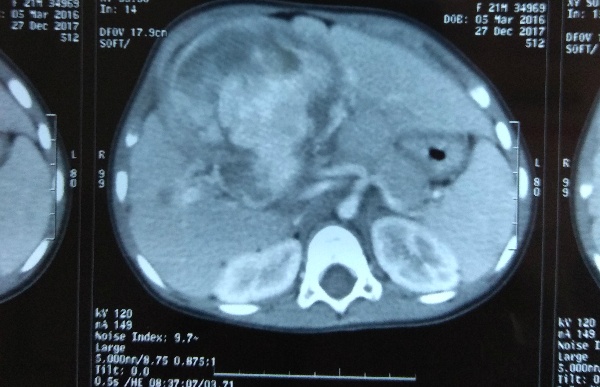

Bé N.H.M.D (2 tuổi) đến Bệnh viện Nhi đồng 2 trong tình trạng bụng lớn nhanh. Qua chụp CT vùng bụng cho thấy một khối u rất lớn chiếm gần lá gan.

| Ảnh chụp khối u gan chiếm gần hết thể tích lá gan bệnh nhi. Ảnh: BVCC |

Bác sĩ lập tức làm sinh thiết khối u. Kết quả cho thấy khối u này là u ác tính sarcoma mạch máu, chiếm 1-2% trong các loại u gan ác tính ở trẻ em. Hiện, y văn thế giới hiện chỉ ghi nhận khoảng 50 trường hợp được công bố.